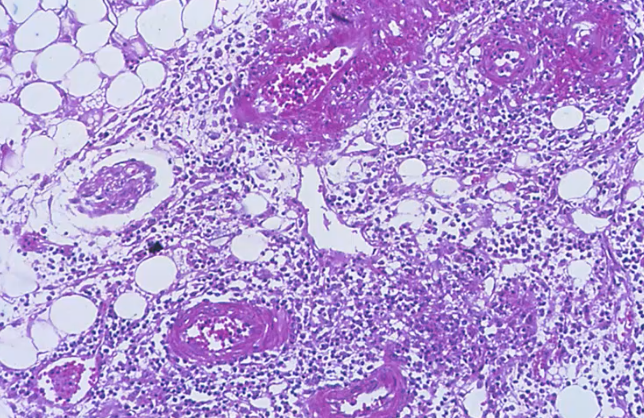

Polyarteritis nodosa

Polyarteritis Nodosa, fibrinoid necrosis

Strong evidence of fibrinoid necrosis, polyarteritis nodosa